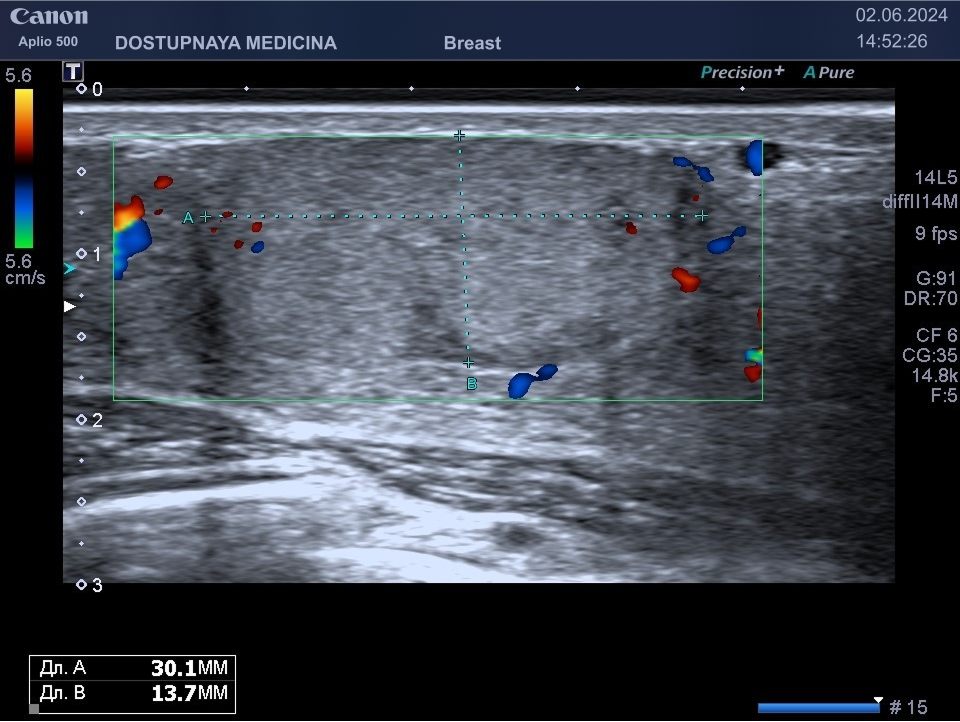

Кисты могут воспаляться, тогда при ультразвуковом исследовании в режиме ЦДК вокруг кисты отмечается усиление кровотока, пациентка при этом жалуется обычно на уплотнение и боль в области кисты молочной железы. Воспаление кисты может привести к её абсцедированию.

При ультразвуковом исследовании в кисте может быть визуализирован папиллярный компонент с кровотоком в режиме ЦДК. Так могут выглядеть цистаденопапилломы, которые считаются аблигатным предраком.